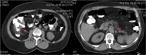

Clostridium perfringens's necrotizing acute pancreatitis: a case of success

Rita Castro and others

Journal of Surgical Case Reports, Volume 2017, Issue 6, June 2017, rjx116, https://doi.org/10.1093/jscr/rjx116